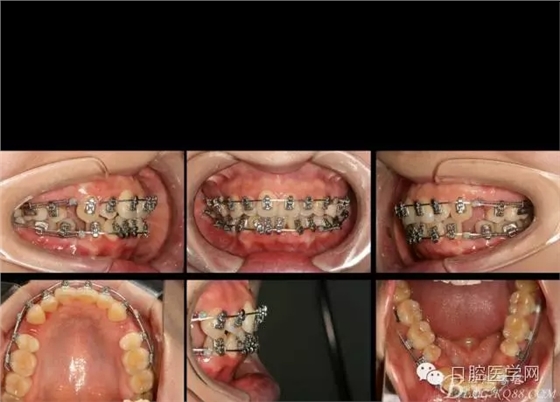

2016.6.7 第二次復(fù)診效果 上頜繼續(xù),只是將弓絲末端變長(zhǎng)的弓絲剪斷重新回彎,其他沒有做任何處理。下頜將右側(cè)的拉簧拆掉,在右下1與3之間推簧,調(diào)整中線,其余沒動(dòng)。

矯正到目前,矯正開始三個(gè)月四天,矯正比較平穩(wěn),拔牙間隙關(guān)閉接近三分之二。矯正效果明顯。每次復(fù)診處理簡(jiǎn)潔,椅旁時(shí)間幾分鐘。大大減少醫(yī)生工作壓力,矯正療程大大縮短,是個(gè)很好的技術(shù)。